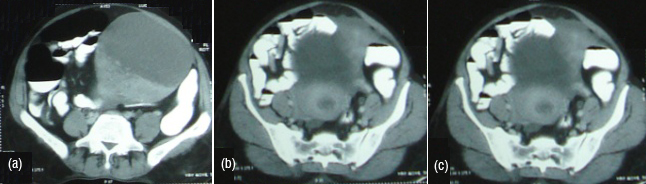

Malignant sex cord tumour and granulosa cell tumour are two types juvenile and adult type. Juvenile present before puberty and present with pseudo puberty. Adult type constitute 90% presenting with abnormal uterine bleeding. Granulosa cell tumour has tendency for hemoperitoneum. Size is variable. Morphology is variable may be cystic to complexly solid. They are associated with endometrial abnormality (Figure 16abc). Sertoli-Leydigcell tumour occur in younger age and tends to be unilateral. Size is variable may appear as solid/ solid with peripheral cyst/ cystic lesion with solid mural component or completely cystic. Well defined enhancing solid tumour with variable intra tumoural cystic component (Figure 17).

Figure 16a,b,c: Granulosa cell tumour.